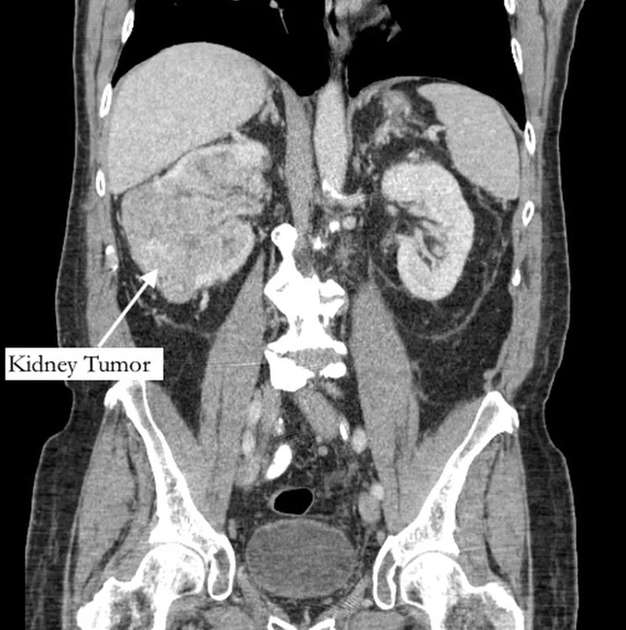

was during a consultation Right big toe pain That retired Richard Bernstein, 42, has been diagnosed with terminal cancer. The case occurred in the United States, after the man received Kidney tumor diagnosis The tumor thrombus. information from g 1.

With the intensification of symptoms, one of the doctors asked a Abdominal examination. In March of this year, he already felt pain in his ankle and swelling in his leg. The examination revealed a tumor that had grown into the renal vein and filled the vena cava.